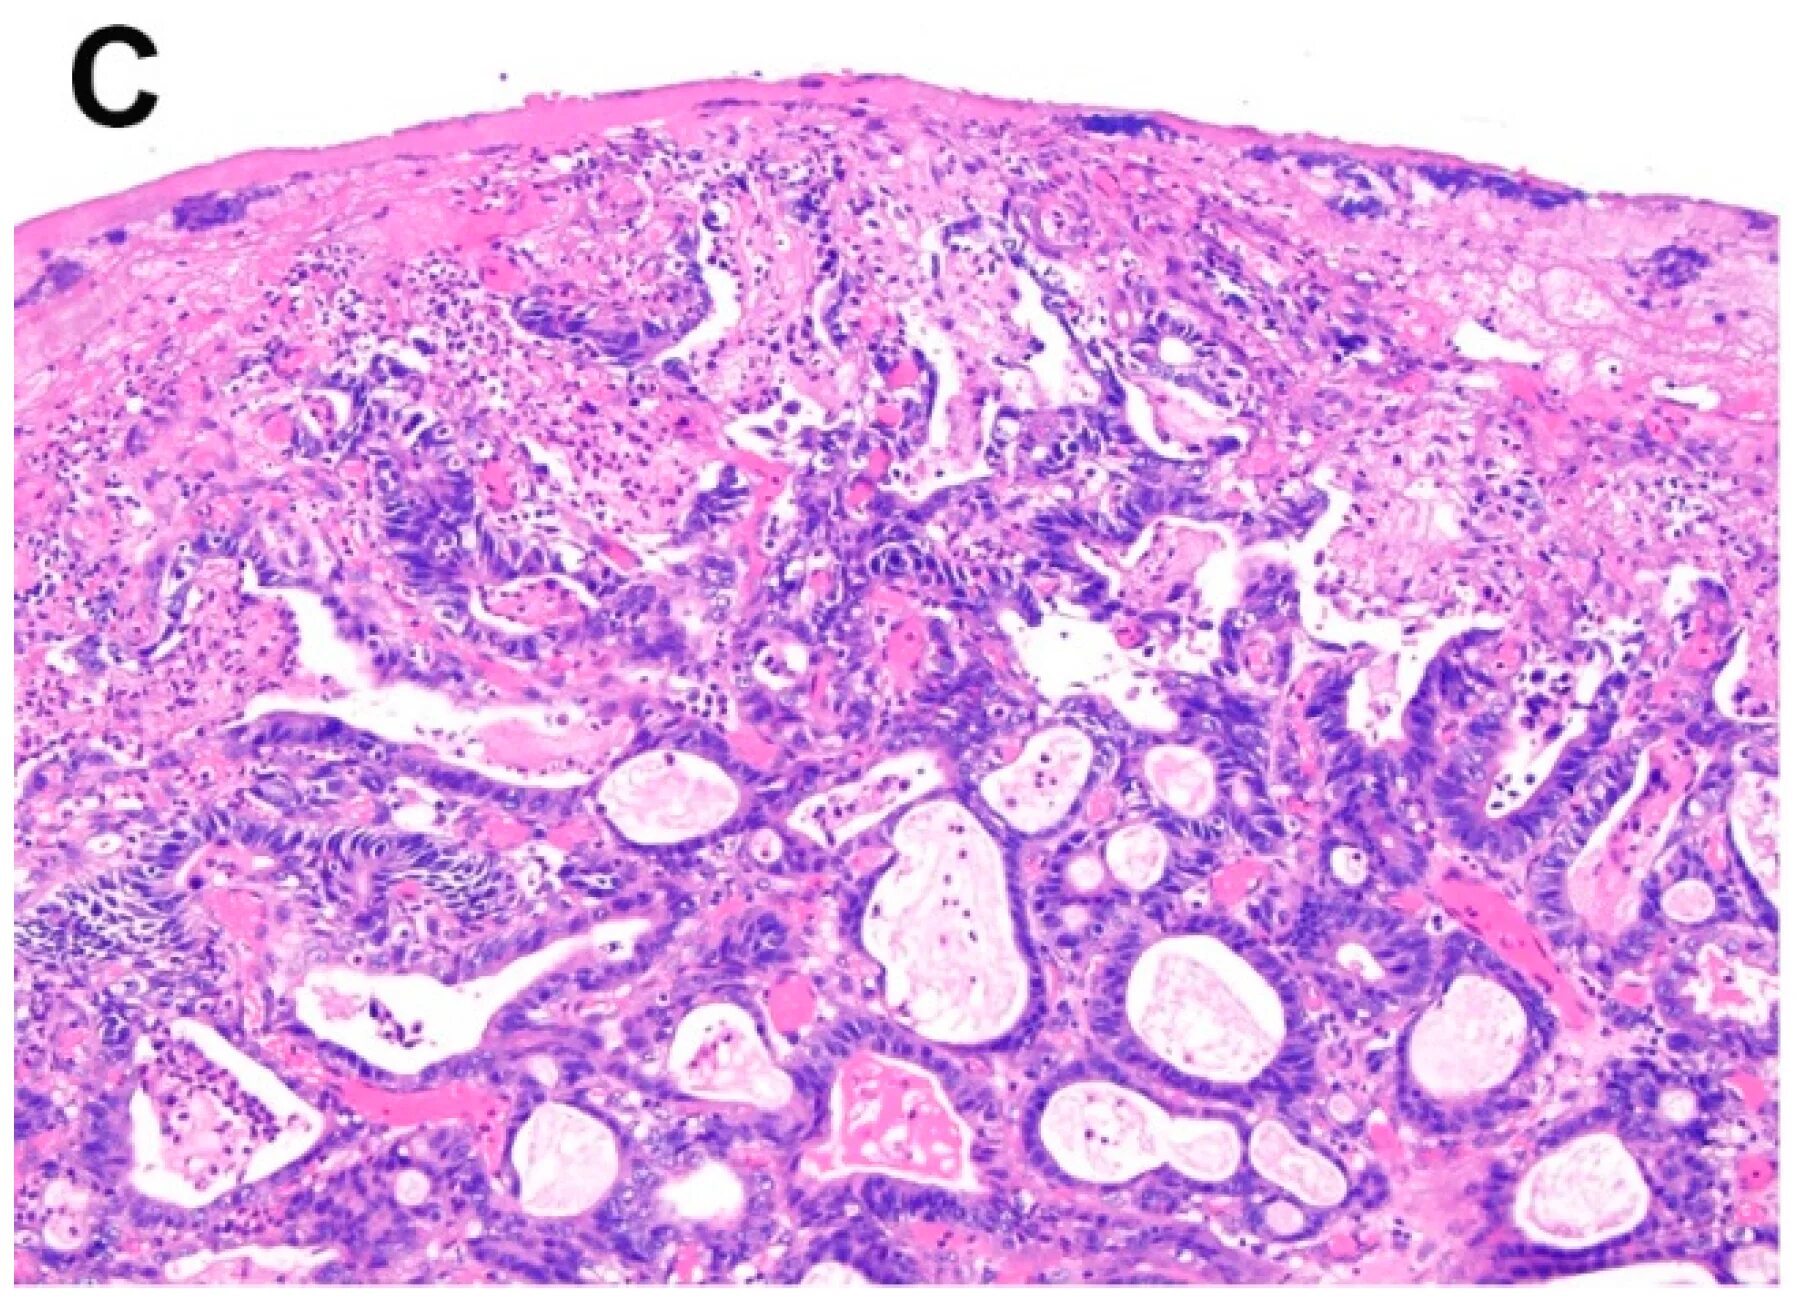

Метастазы рака почки